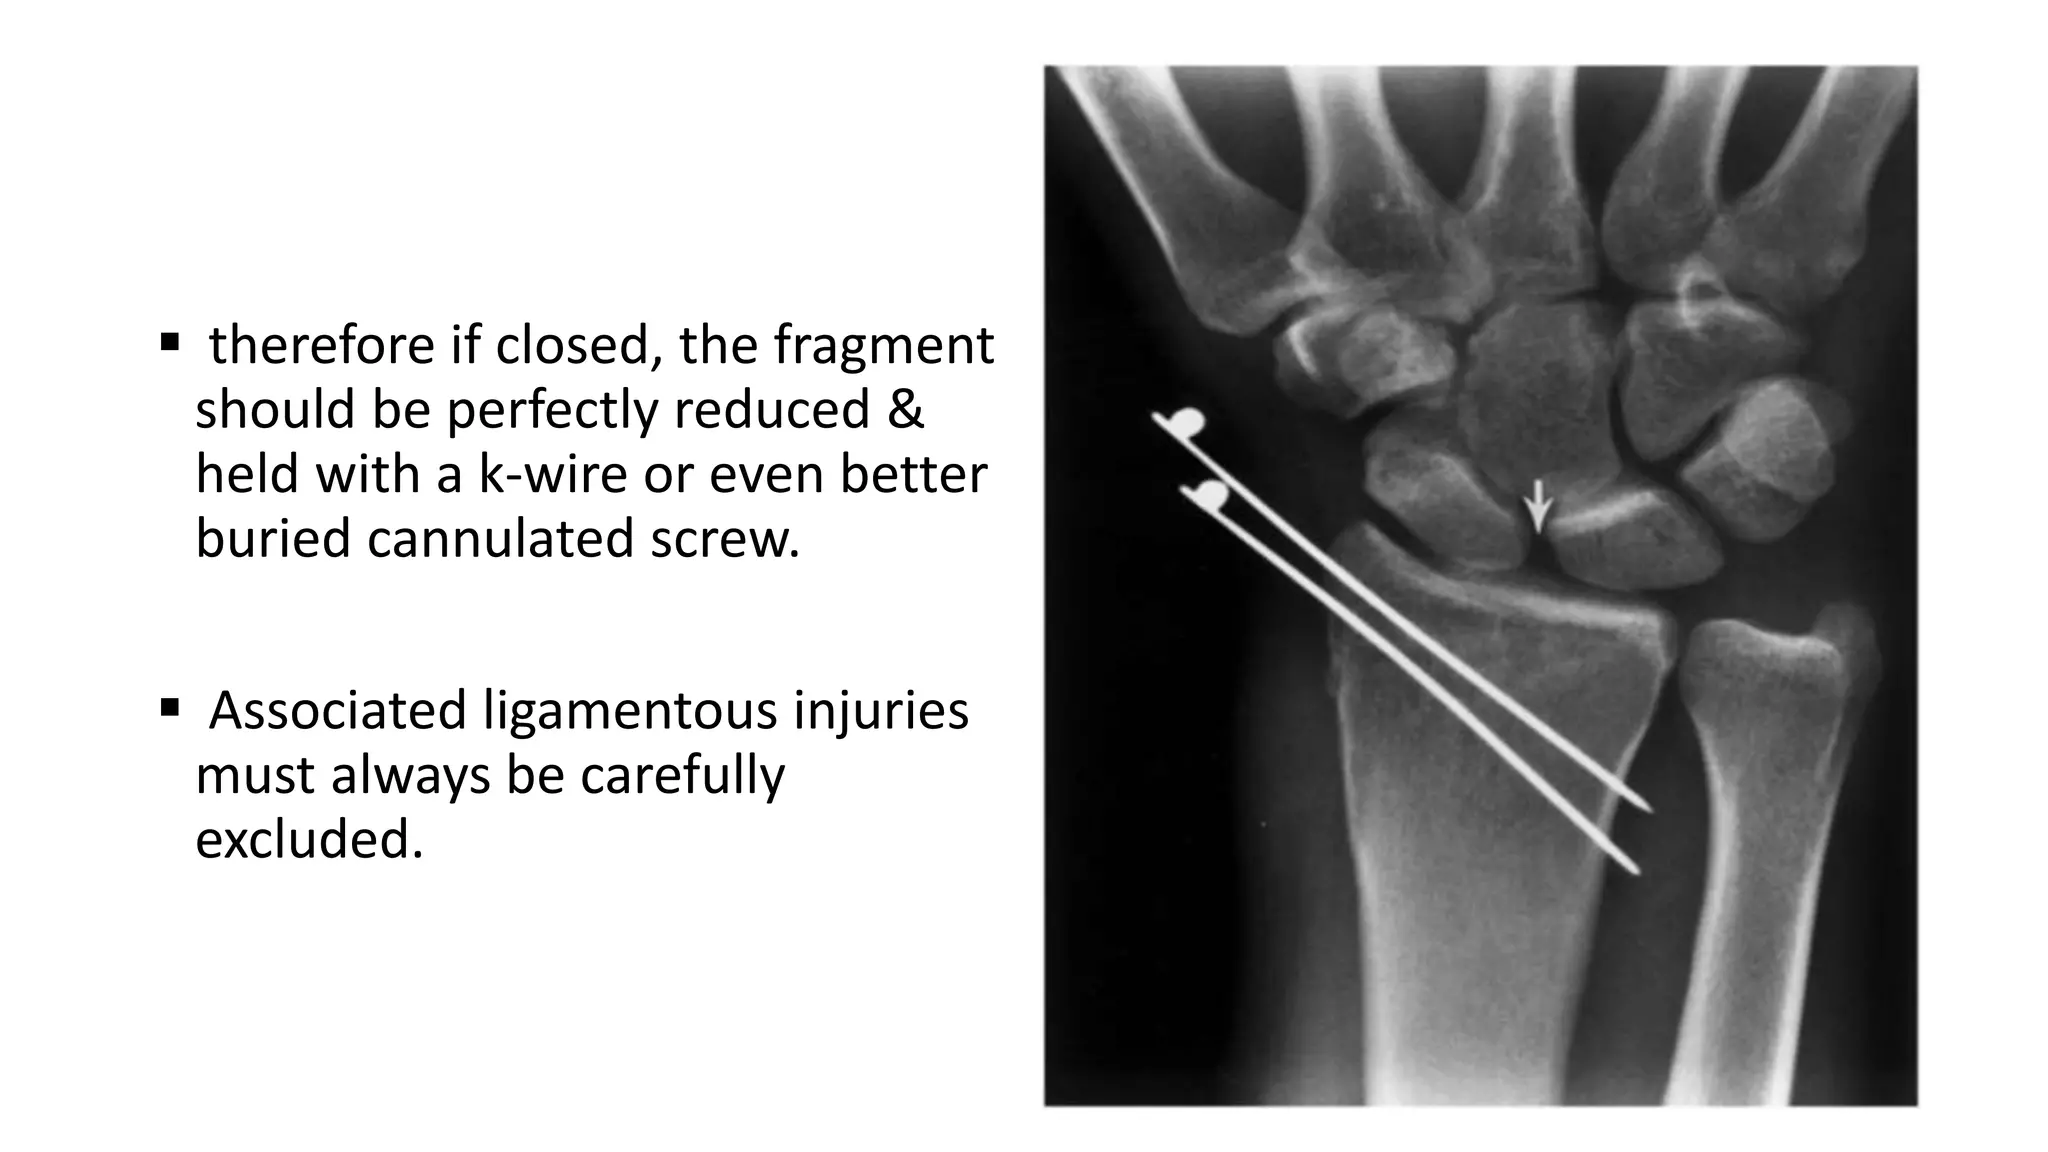

 therefore if closed, the fragment

should be perfectly reduced &

held with a k-wire or even better

buried cannulated screw.

 Associated ligamentous injuries

must always be carefully

excluded.

• 45.

 therefore ifclosed, the fragment should be perfectly reduced & held with a k-wire or even better buried cannulated screw.  Associated ligamentous injuries must always be carefully excluded.